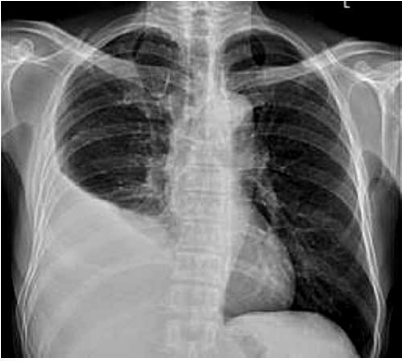

Paciente de 28 anos, procedente de zona de garimpo,

tabagista e etilista, apresenta queixa de tosse seca e dor

torácica à direita há trinta dias, com febre esporádica.

Apresenta episódios de tosse com secreção amarelada

e laivos de sangue há dez dias, sem melhora ou piora.

Emagreceu 6 kg no período de quarenta dias. Exame

físico: emagrecido, Tax: 37,4 ºC, submacicez e murmúrio

vesicular diminuído em base do hemitórax direito.

Radiografia de tórax a seguir: